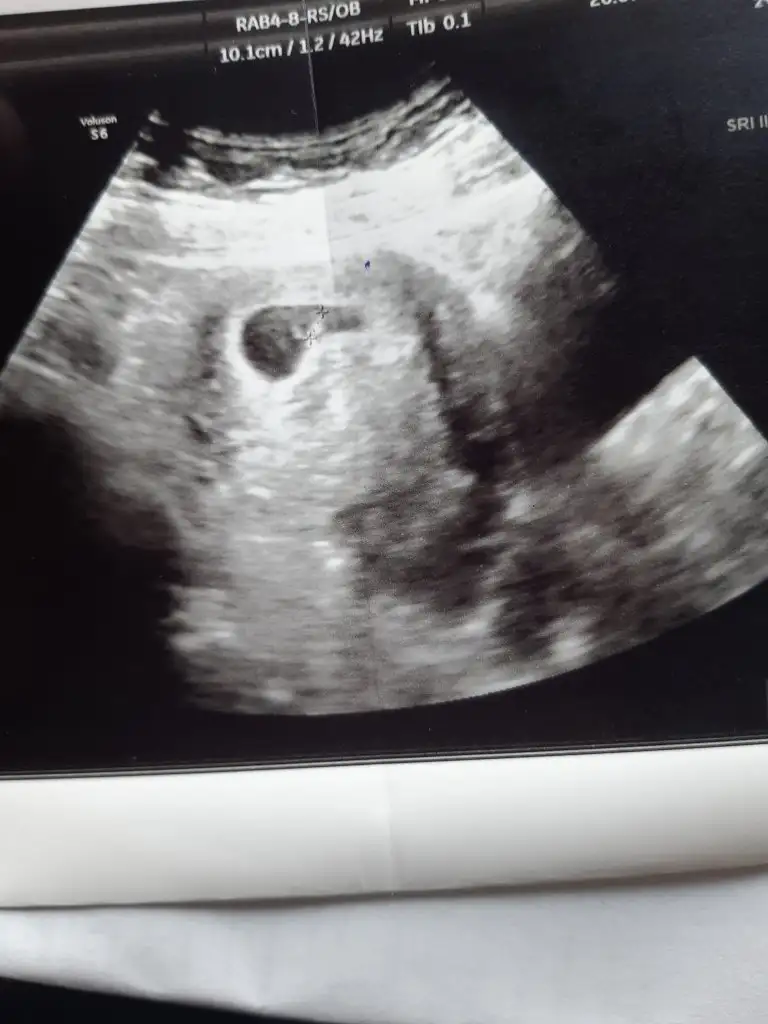

Maşallah canim gözün aydınMerhabaa bugün doktora gittim miniğimin kalbini de duydum kendini de gördüm çok şükür

Gözün aydın canım amin cümlemizinSlm kızlar. Bizde kontrolden çıktık. 6+6 olmuş bebeğim. Kalp atımını duyduk çok şükür. Allahım isteyen herkese nasip etsin. Sağlıklı sıhhatli alalım bebişlerimizi kucağımıza inşallah![]()

Bugun doktor kontrolüne gittik. Tam 7 haftalik kalp atisini karından duyduk. Haftasiyla uyumlu dedi. 9. Haftada gormek isteriz. 10. Haftada da nifty yaptırırsin dedi. Kan sulandirici igne ve folik asite devam.